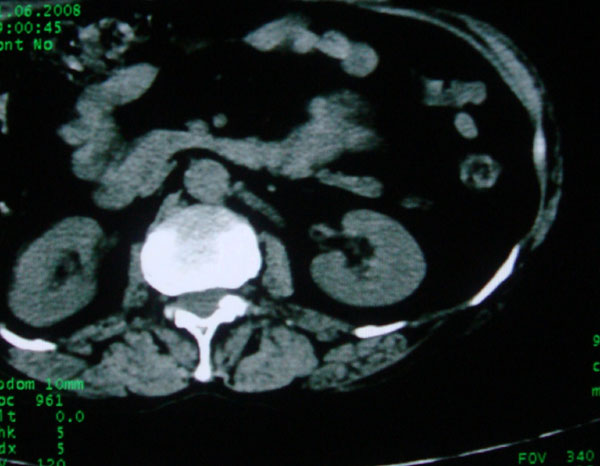

患者女性体查.发现左肾有低密度影,大家考虑是什么.其它方面没有什么异常.低密度影ct值约22hu.

左肾低密度影,境界尚清,查体发现,临床无其他首先考虑肾囊肿,如果增强一下对鉴别有帮助。

左肾不均匀低密度,其形态不规则、边界不清楚,更谈不上锐利。虽无局部凸出,但最后一张片显示仍有比较明显的隆起,我多考虑为肾癌,建议增强或mri检查。